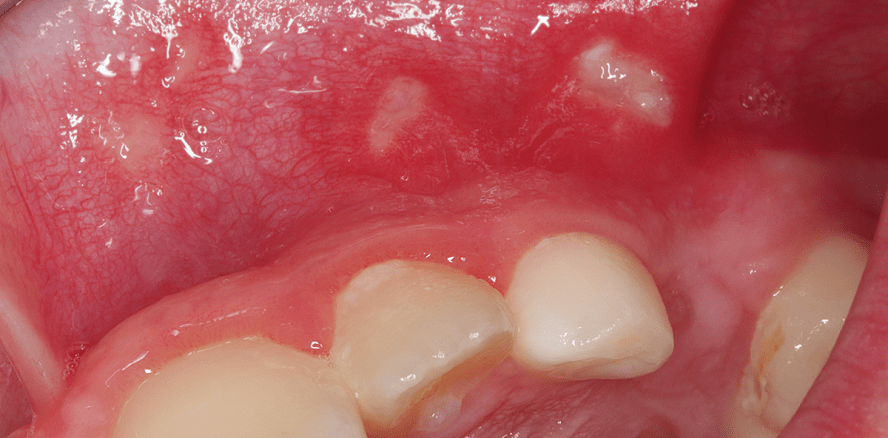

Chronische rezidivierende Aphthen

Chronische rezidivierende Aphthen sind häufige Mundschleimhautveränderungen, die 25 bis 66 % der Menschen betreffen.1 Meistens treten diese Veränderungen erst ab dem 10. Lebensjahr auf. Jedoch können chronisch rezidivierende Aphthen auch bei Kindern auftreten, bei 40 % schon vor dem 5. Lebensjahr.2

Klinisch können die Aphthen in drei Formen eingeteilt werden.3 Die Minor­variante kommt am häufigsten vor (80 %). Es handelt sich um bis zu 5 mm große rundlich-ovale Ulzerationen, die eine fibrinbelegte graue Oberfläche und einen geröteten Randsaum (Halo) aufweisen. Typischerweise treten Minor­aphthen an der nicht keratinisierten Gingiva im Bereich von Wange, Mundboden und Umschlagfalte, seltener an Gingiva und Gaumen auf. Meistens heilen sie nach ein bis zwei Wochen narbenfrei ab (Abb. 1 und 2). Die seltenen Majoraphthen sind größer als 1 cm. Meistens finden sie sich an den Lippen, am Weichgaumen und am Gaumenbogen. Da die Ulzeration bis in tiefere Gewebsschichten reicht, heilen diese Aphthen typischerweise unter Narbenbildung nach sechs bis acht Wochen ab. Herpetiforme Aphthen sind selten. Klinisch ähneln sie den Minoraphthen. Sie treten jedoch in der gesamten Mundhöhle an bis zu 100 Stellen auf.4,5

Klinisch finden sich bei der Soorinfektion enoral weißliche, gut verschiebbare Beläge mit rotem Randsaum (Abb. 6). Eventuell besteht ein Foetor ex ore. Die Symptomatik zeigt Schleimhautbrennen, Trockenheitsgefühl und Hypgeusie.